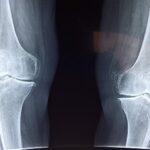

Diagnosis of the arthropathy component relies on a combination of clinical history, imaging, and supportive biochemical or genetic testing. Plain radiographs may demonstrate joint space narrowing, calcified cartilage or discs, osteophyte formation, and, in the spine, disc degeneration with calcification. Advanced imaging (such as MRI) may show cartilage damage and pigment deposition in connective tissues. Laboratory testing revealing elevated homogentisic acid in urine confirms the underlying metabolic disorder. Genetic testing may identify mutations in the relevant gene. A full assessment should include evaluation of other systemic complications (cardiac valves, kidneys, spine), given the systemic nature of the disease.